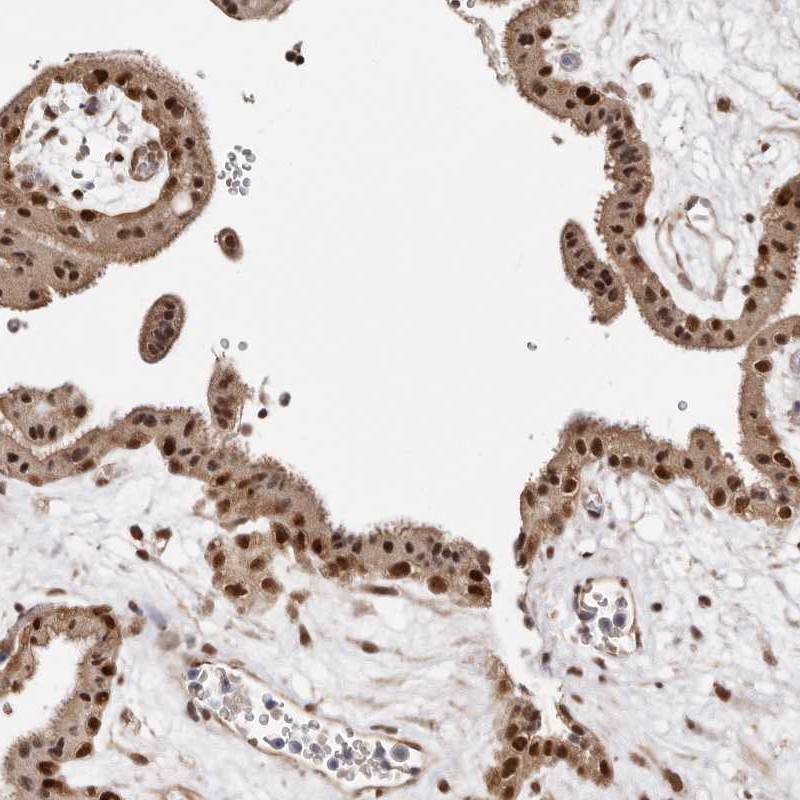

Immunohistochemical staining of human placenta shows strong nuclear positivity in trophoblastic cells.